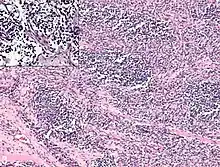

Alveolar

Alveolar rhabdomyosarcoma (ARMS) is the second-most common type. ARMS comprises around 20–25% of RMS-related tumors, and it is equally distributed among all age groups with an incidence of about one case per million people ages 0 to 19. For this reason, it is the most common form of RMS observed in young adults and teenagers, who are less prone to the embryonal variant. This type of RMS is characterized by densely packed, round cells that arrange around spaces similar in shape to pulmonary alveoli, although variants have been discovered without these characteristic alveolar spacings. ARMS tends to form more often in the extremities, trunk, and peritoneum. It is also typically more aggressive than ERMS.[12][15]